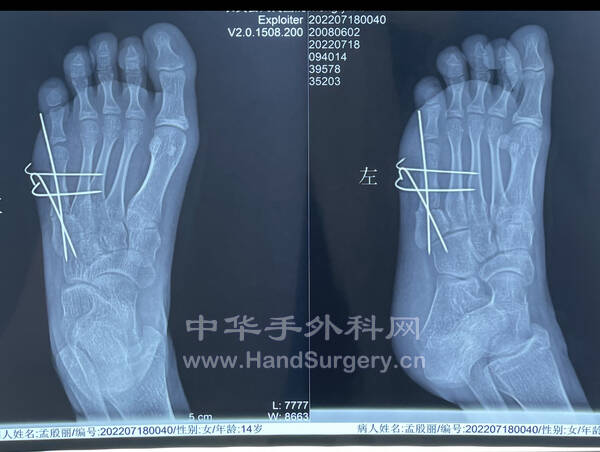

患者女性,14岁,先天双足多趾畸形。

术后x线片 165F257A-1A12-40B8-8A3A-C5AB5EDE96C6.jpeg 60FF939C-D716-474F-B1E3-FBC1FC7F8BFB.jpeg